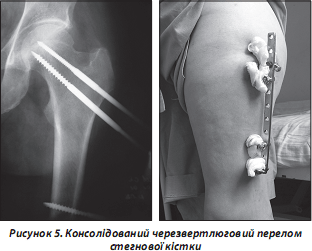

Також для остеосинтезу уламків використовується стрижневий апарат зовнішньої фіксації (рис. 5). Особливість застосування апарату пов’язана з необхідністю ретельного догляду за місцями входу стрижнів у м’які тканини. Рухомість їх при недотриманні правил асептики досить швидко викликає інфікування довкола стрижнів з необхідністю їх видалення або перепроведення.